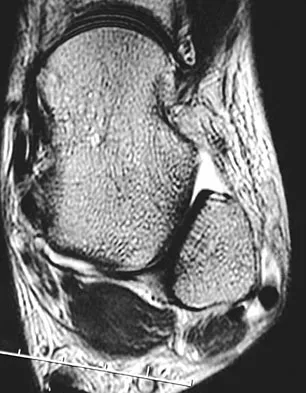

A 44-year-old recreational weight lifter reports chronic deep pain in his left shoulder that is aggravated by any pressing exercises. He also notes a painful catch in the shoulder occurring with rotational movements. Physical therapy and nonsteroidal anti-inflammatory drugs for 3 months have failed to provide relief. Examination reveals pain with O'Brien's test but no signs of instability. MRI scans are shown in Figures 4a and 4b. Treatment should now consist of

Explanation

The MRI scans show a large paralabral ganglion cyst in the spinoglenoid notch that communicates with an extensive tear of the glenoid labrum. Snyder and associates have classified superior labral tears into several subtypes that reflect the location and extent of the injury. Arthroscopic repair of the labral tear and aspiration of the ganglion cyst is the treatment of choice. Open excision of the cyst does not address the underlying problem of the labral tear. Snyder SJ, Karzel RP, Delpizzo W: SLAP lesions of the shoulder. Arthroscopy 1990;6:274-279. Piatt BE, Hawkins RJ, Fritz RC, et al: Clinical evaluation and treatment of spinoglenoid notch cysts. J Shoulder Elbow Surg 2002;11:600-604. McFarland EG, Kim TK, Savino RM: Clinical assessment of three common tests for superior labral anterior-posterior lesions. Am J Sports Med 2002;30:810-815.